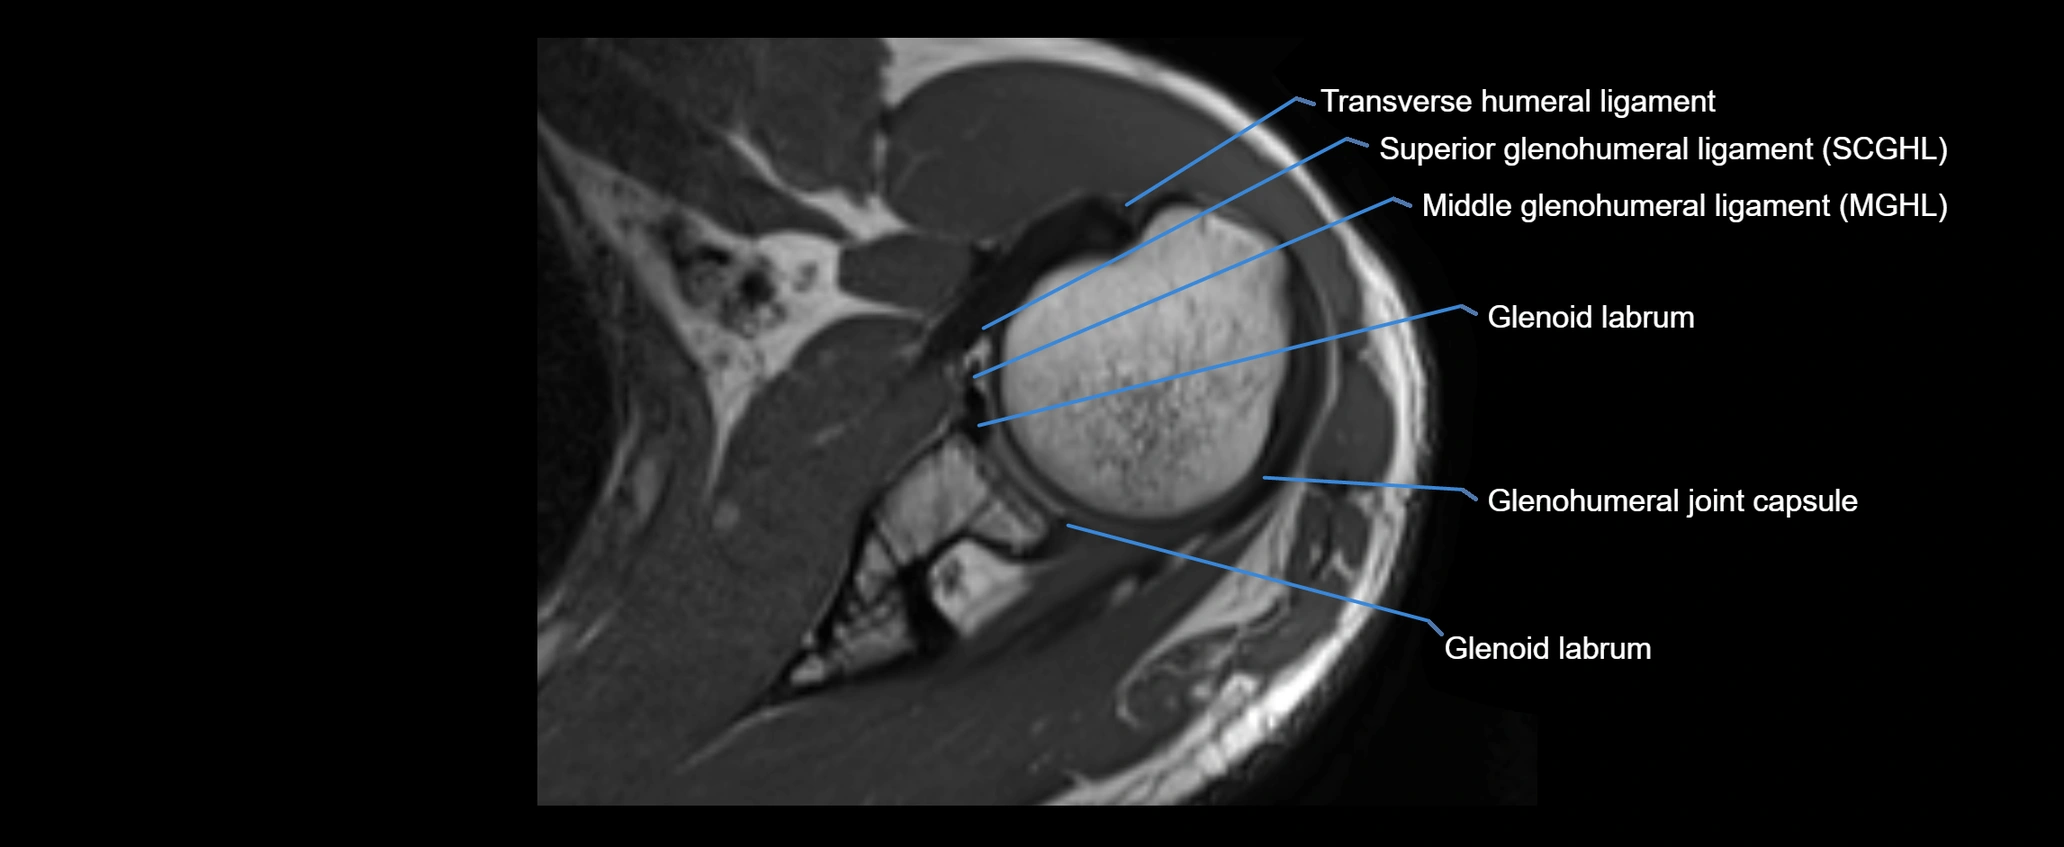

CT image

image